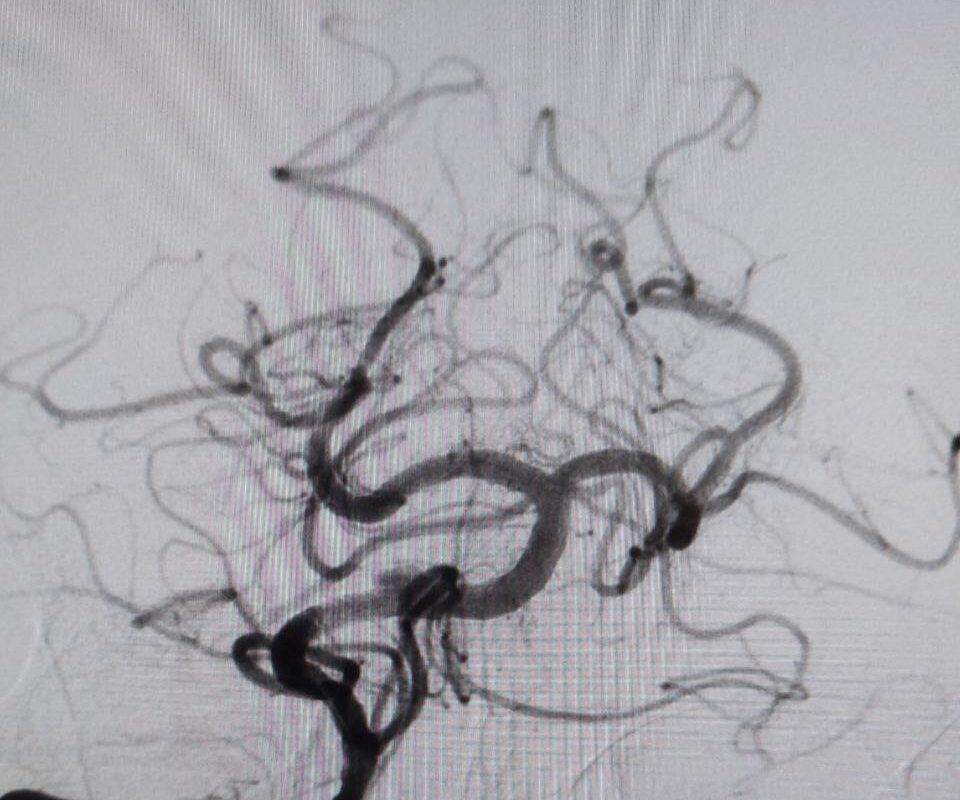

«В ходе обследования врачи диагностировали закупорку основной артерии, обеспечивающий кровоснабжение важнейших отделов головного мозга. Это очень тяжелое состояние с крайне высокой летальностью», — пояснили врачи.

Мужчине провели экстренную операцию, в ходе которой удалили тромб и установили стент.